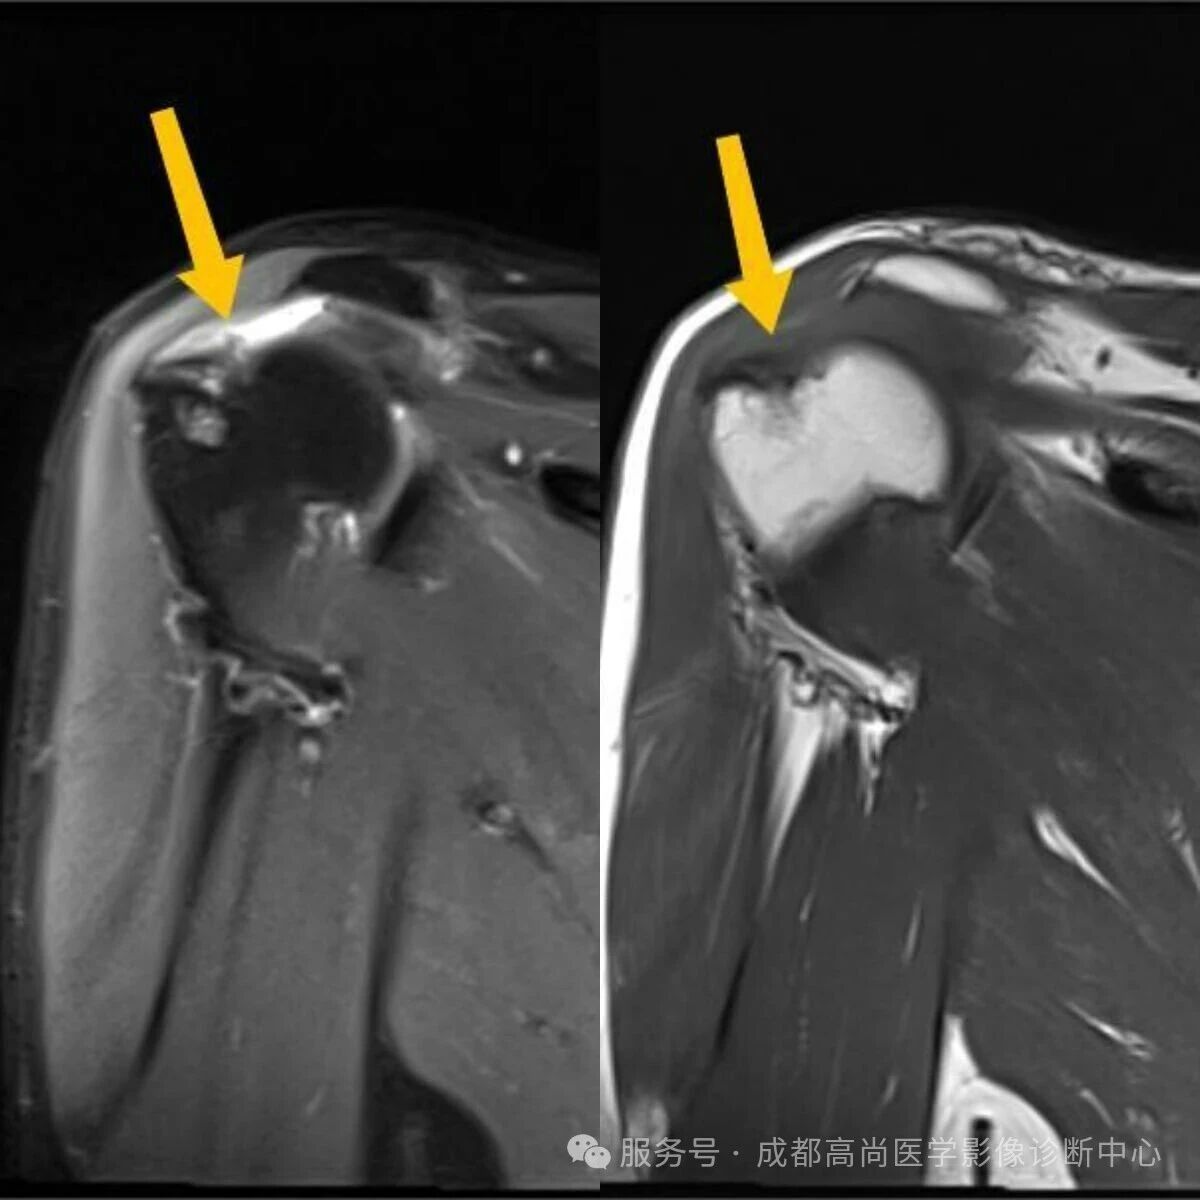

右肩 MRI 检查图像

图 1—5 MRI 平扫示右肩冈上肌肌腱失去正常形态结构,局部显示欠连续,肌腱附着点未见正常结构显示,提示冈上肌腱断裂。

A. 正常冈上肌腱前部;B. 正常冈上肌腱中部层面;C. 冈上肌腱变性;D. 冈上肌腱中部完全撕裂;E. 冈上肌腱滑囊面部分撕裂;F. 冈上肌腱关节面部分撕裂